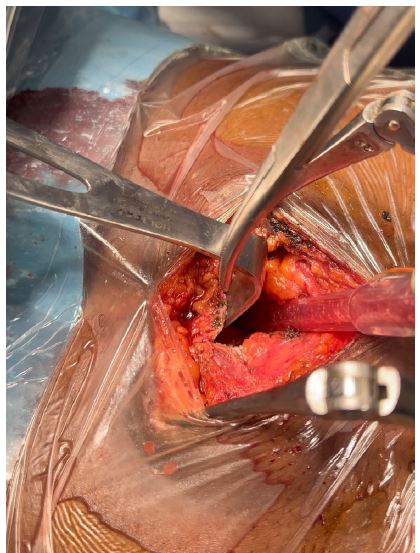

Figure 3: Showing surgical site with pericardiotomy.

Figure 4: Showing surgical site with curved clamp showing amputated xiphoid process